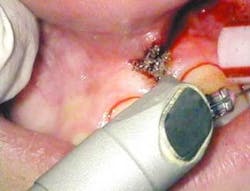

After infiltration of 1cc of local anesthetic solution, the Er:YAG laser (OpusDuo, OpusDent USA) was used at 350mj with a 1,000-micron, contact sapphire tip and heavy water spray to gently ablate the frenal attachment and underlying muscle tissue down to the level of the periosteum (figures 2, 3, and 4). Once this is accomplished, there is a small defect in the vestibular mucosa and interdental papilla where the frenal attachment and muscle once was. There is no charring, no burned tissue, and free bleeding in the site (figure 5).

Once the Erbium part of the procedure is completed, the Superpulsed CO2 (OpusDuo, Opusdent USA) is then used to simply coagulate and gently cauterize the bleeding site. With this approach, the practitioner can immediately pick up a focused 90-degree handpiece and apply 1.5 watts in the Superpulsed noncontact mode. This is accomplished with a circular sweeping pattern to gently coagulate the superficial bleeding layer to a depth of 75-100 microns (figures 6 and 7).